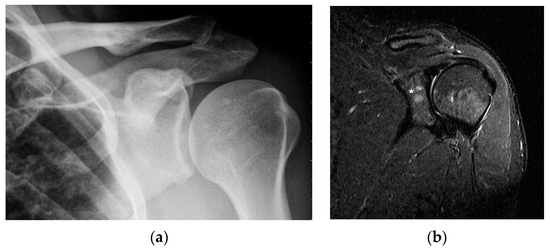

MR is a highly sensitive imaging modality that can detect bone marrow involvement in sarcoidosis. It also provides the detailed information on soft tissue involvement, synovitis and joint inflammation. Occasionally, MR images detect clinically and radiologically silent lesions (Figure 3a,b).

Chronic arthritis, either mono-articular or poly-articular, occurs in the later phases of the disease, usually as a part of a multisystem manifestation. In addition to synovitis (Figure 5a,b), erosions of the articular surfaces may be present, making it necessary to differentiate the lesions from reactive or rheumatoid arthritis [19]. An additional difficulty is that the rheumatoid factor may be positive in 10–47% of cases [20]. If differential diagnosis is necessary, a synovial US-guided biopsy is performed. Detection of granulomas in a synovial biopsy sample helps make the diagnosis of sarcoidosis [20]. X-ray shows soft tissue swelling and epiphyseal demineralization.

Long-lasting joint inflammation leads to the narrowing of the joint space. In the sarcoid arthritis diagnostic imaging, we mainly use X-ray, US, and MR imaging. MRI shows with high sensitivity the joint effusion and features of synovitis, cartilage destruction, and inflammatory changes of periarticular structures such as peritendinitis, tendinitis or bursitis (Figure 5a,b) [20].

Figure 3. Radiograph (a) and magnetic resonance of the shoulder joint. T1-weighted image with fat saturation and with contrast administration (b). 40-year-old patient with sarcoidosis. Two contrast-enhanced lesions in the acetabulum of the joint ((b), asterisk) not visible on X-ray (a).